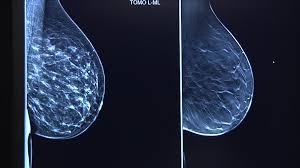

What Does Breast Cancer Look Like On A 3D Mammogram / Mammogram Images Normal And Abnormal - Treatment typically involves some type of surgery and depends upon the staging of the.. The tumor cells don't stay within the clear borders of the mass, but instead invade the nearby breast tissue. The look of breast cancer on a mammogram a tumor or lump will appear as a focused white area on the mammogram. Tumors may be benign or cancerous. Rather than an image that is formed from pictures taken from top to bottom and side to side like a. 3d mammography, or breast tomosynthesis, is a relatively new breast imaging procedure approved by the u.s.

Dense breast tissue appears solid. Essentially, mammograms turn a 3d object into a 2d object. Finding breast lumps and seeing change in the size and shape. Ultimately, the news is good: A number of studies have found that 3d mammograms find more cancers than traditional 2d mammograms and also reduce the number of false positives. A mammogram can show breast changes such as calcifications, masses, or other symptoms that might be cancer. Calcifications are calcium deposits within the breast tissue and they look like small white spots. Digital breast tomosynthesis (tomo), also known as 3d mammography, is a revolutionary new screening and diagnostic breast imaging tool to improve the early detection of breast cancer. American cancer society, 9 oct 2017. Ultrasound characterization of breast masses. indian journal of radiology and imaging. However, when the breast is compressed from top to bottom, the tissue in the upper breast can overlap tissue in the lower breast. Any area that does not look like normal tissue is a possible cause for concern. It appears to be developing in a concentric pattern.